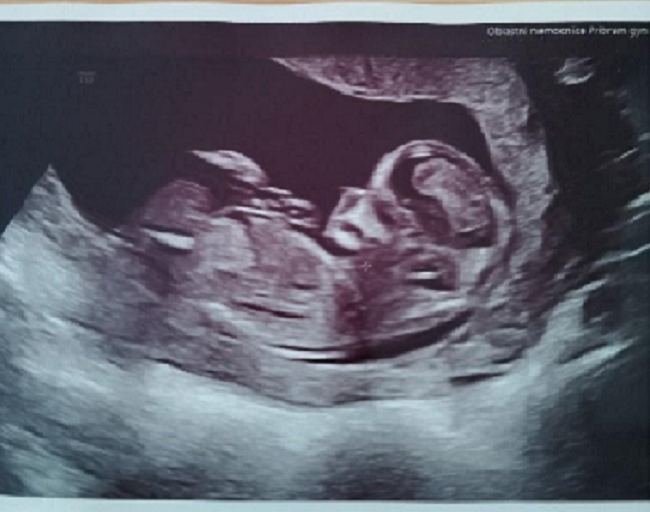

Dobrý den, pokud je váš cyklus 33 dní, pak ovulace probíhá pravděpodobně později než 14. den cyklu, tedy datum 5.1. je nepravděpodobné. Zpětně lze den oplodnění (pokud je úspěšné) zjistit dle velikosti plodu na UZ.